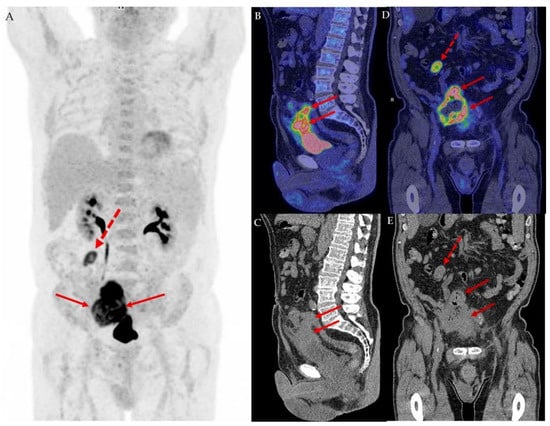

Two histopathological images of urothelial carcinoma, H&E, low magnification (A), and GATA3, high magnification (B).